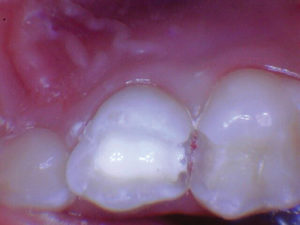

Un nuevo paciente de 7 años presentó una importante descomposición e hipocalcificación en el primer molar permanente superior derecho. Durante mucho tiempo se ha demostrado que los primeros molares permanentes cariados e hipocalcificados en pacientes pediátricos le dan al profesional un dilema restaurador difícil. ¿Deberíamos intentar prepararnos y restaurarlos conservadoramente? ¿Deberíamos ser más agresivos y restaurar con una cobertura completa como una corona de acero inoxidable bien adaptada? Activa proporciona una gran alternativa en estos casos, con liberación de calcio, fosfato y fluoruro junto con alta resistencia y resistencia a la fractura.

Figura 2. Una vez que se excavó la descomposición y se colocaron los márgenes en superficies sólidas, se colocó un bisel pesado en el esmalte para aumentar la resistencia de la unión y la integridad marginal. El área oscura central era sólida. El diente estaba revestido con una base / revestimiento Activa. |

|